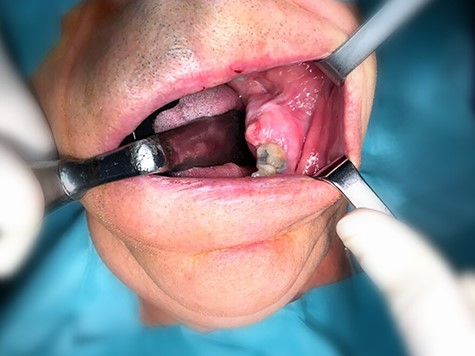

A 79-year-old man came to our department complaining of a painless swelling in the posterior region of the mandible, with uncertain beginning. The mandible in the left molar region was expanded to the buccal and lingual sides (Fig. 1). No fluctuation of the mandible or hypoesthesia of the lower lip was detected.